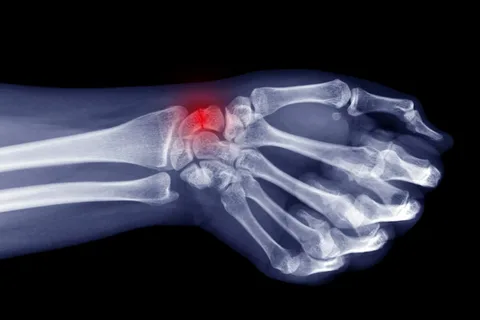

El bileği kırığı (radius distal kırığı), ön kol kemiği olan radius’un bileğe yakın kısmında meydana gelen bir kırık türüdür.

Bu yaralanma genellikle düşme, trafik kazası, spor yaralanması veya ani darbe sonucu oluşur.

• Colles Kırığı: Düşme sonucu elin geriye doğru bükülmesiyle oluşur.

• Smith Kırığı: Elin içe doğru bükülmesiyle meydana gelir.

• Intraartiküler Kırık: Eklem yüzeyini etkileyen ciddi kırıklardır.

Kırığın tipi, tedavi süresini ve fizik tedavi programının içeriğini belirleyen en önemli faktördür.